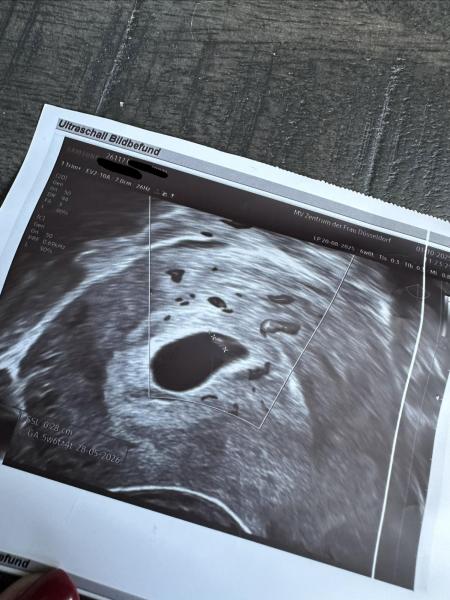

ich hoffe, es geht euch gut! Ich bin ganz neu hier umd momentan in der aufregenden Phase meiner Schwangerschaft. Ich habe heute mein erstes Ultraschallbild erhalten. Ich bin bei 6+0 und es wurde ein winziges Embryo sichtbar, aber leider konnte man den Herzschlag noch nicht wirklich erkennen. Mein Frauenarzt sagt es sei aber gut entwickelt und es schaut alles super aus. Er hat mir nun für nächste Woche einen weiteren Termin gegeben.